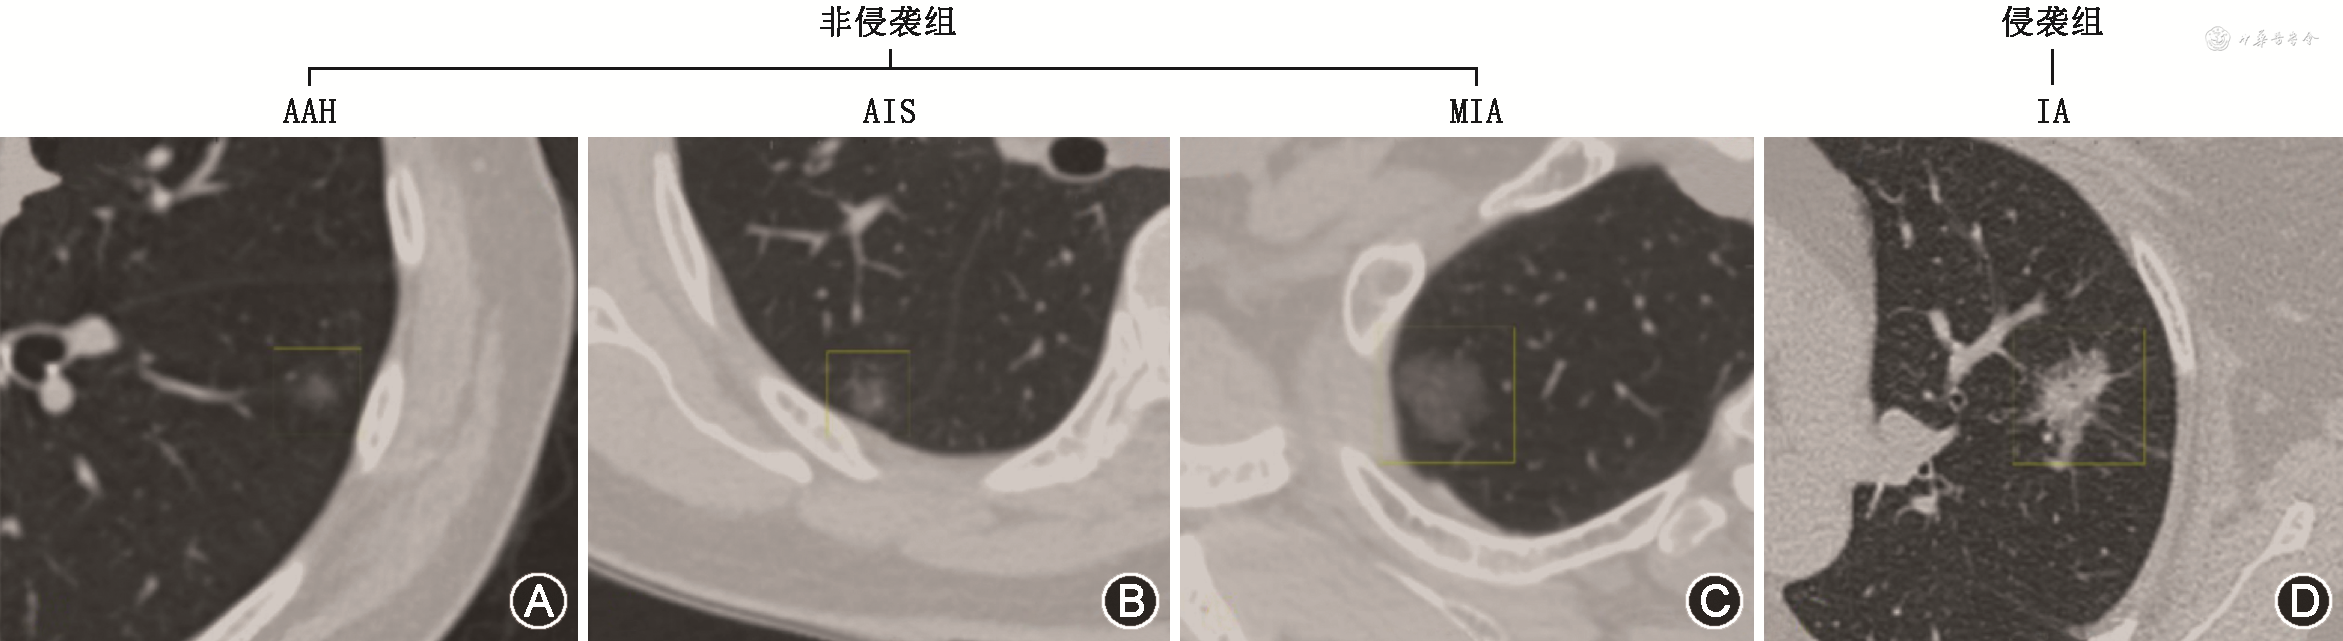

本研究中将 IA 归为侵袭组,将 AAH、AIS、MIA归为非侵袭组[3,5, 6, 7](图1)。

注:AAH为不典型瘤样增生,AIS为原位腺癌,MIA为微浸润性腺癌,IA为浸润性腺癌;非侵袭组包括AAH、AIS、MIA,侵袭组包括IA